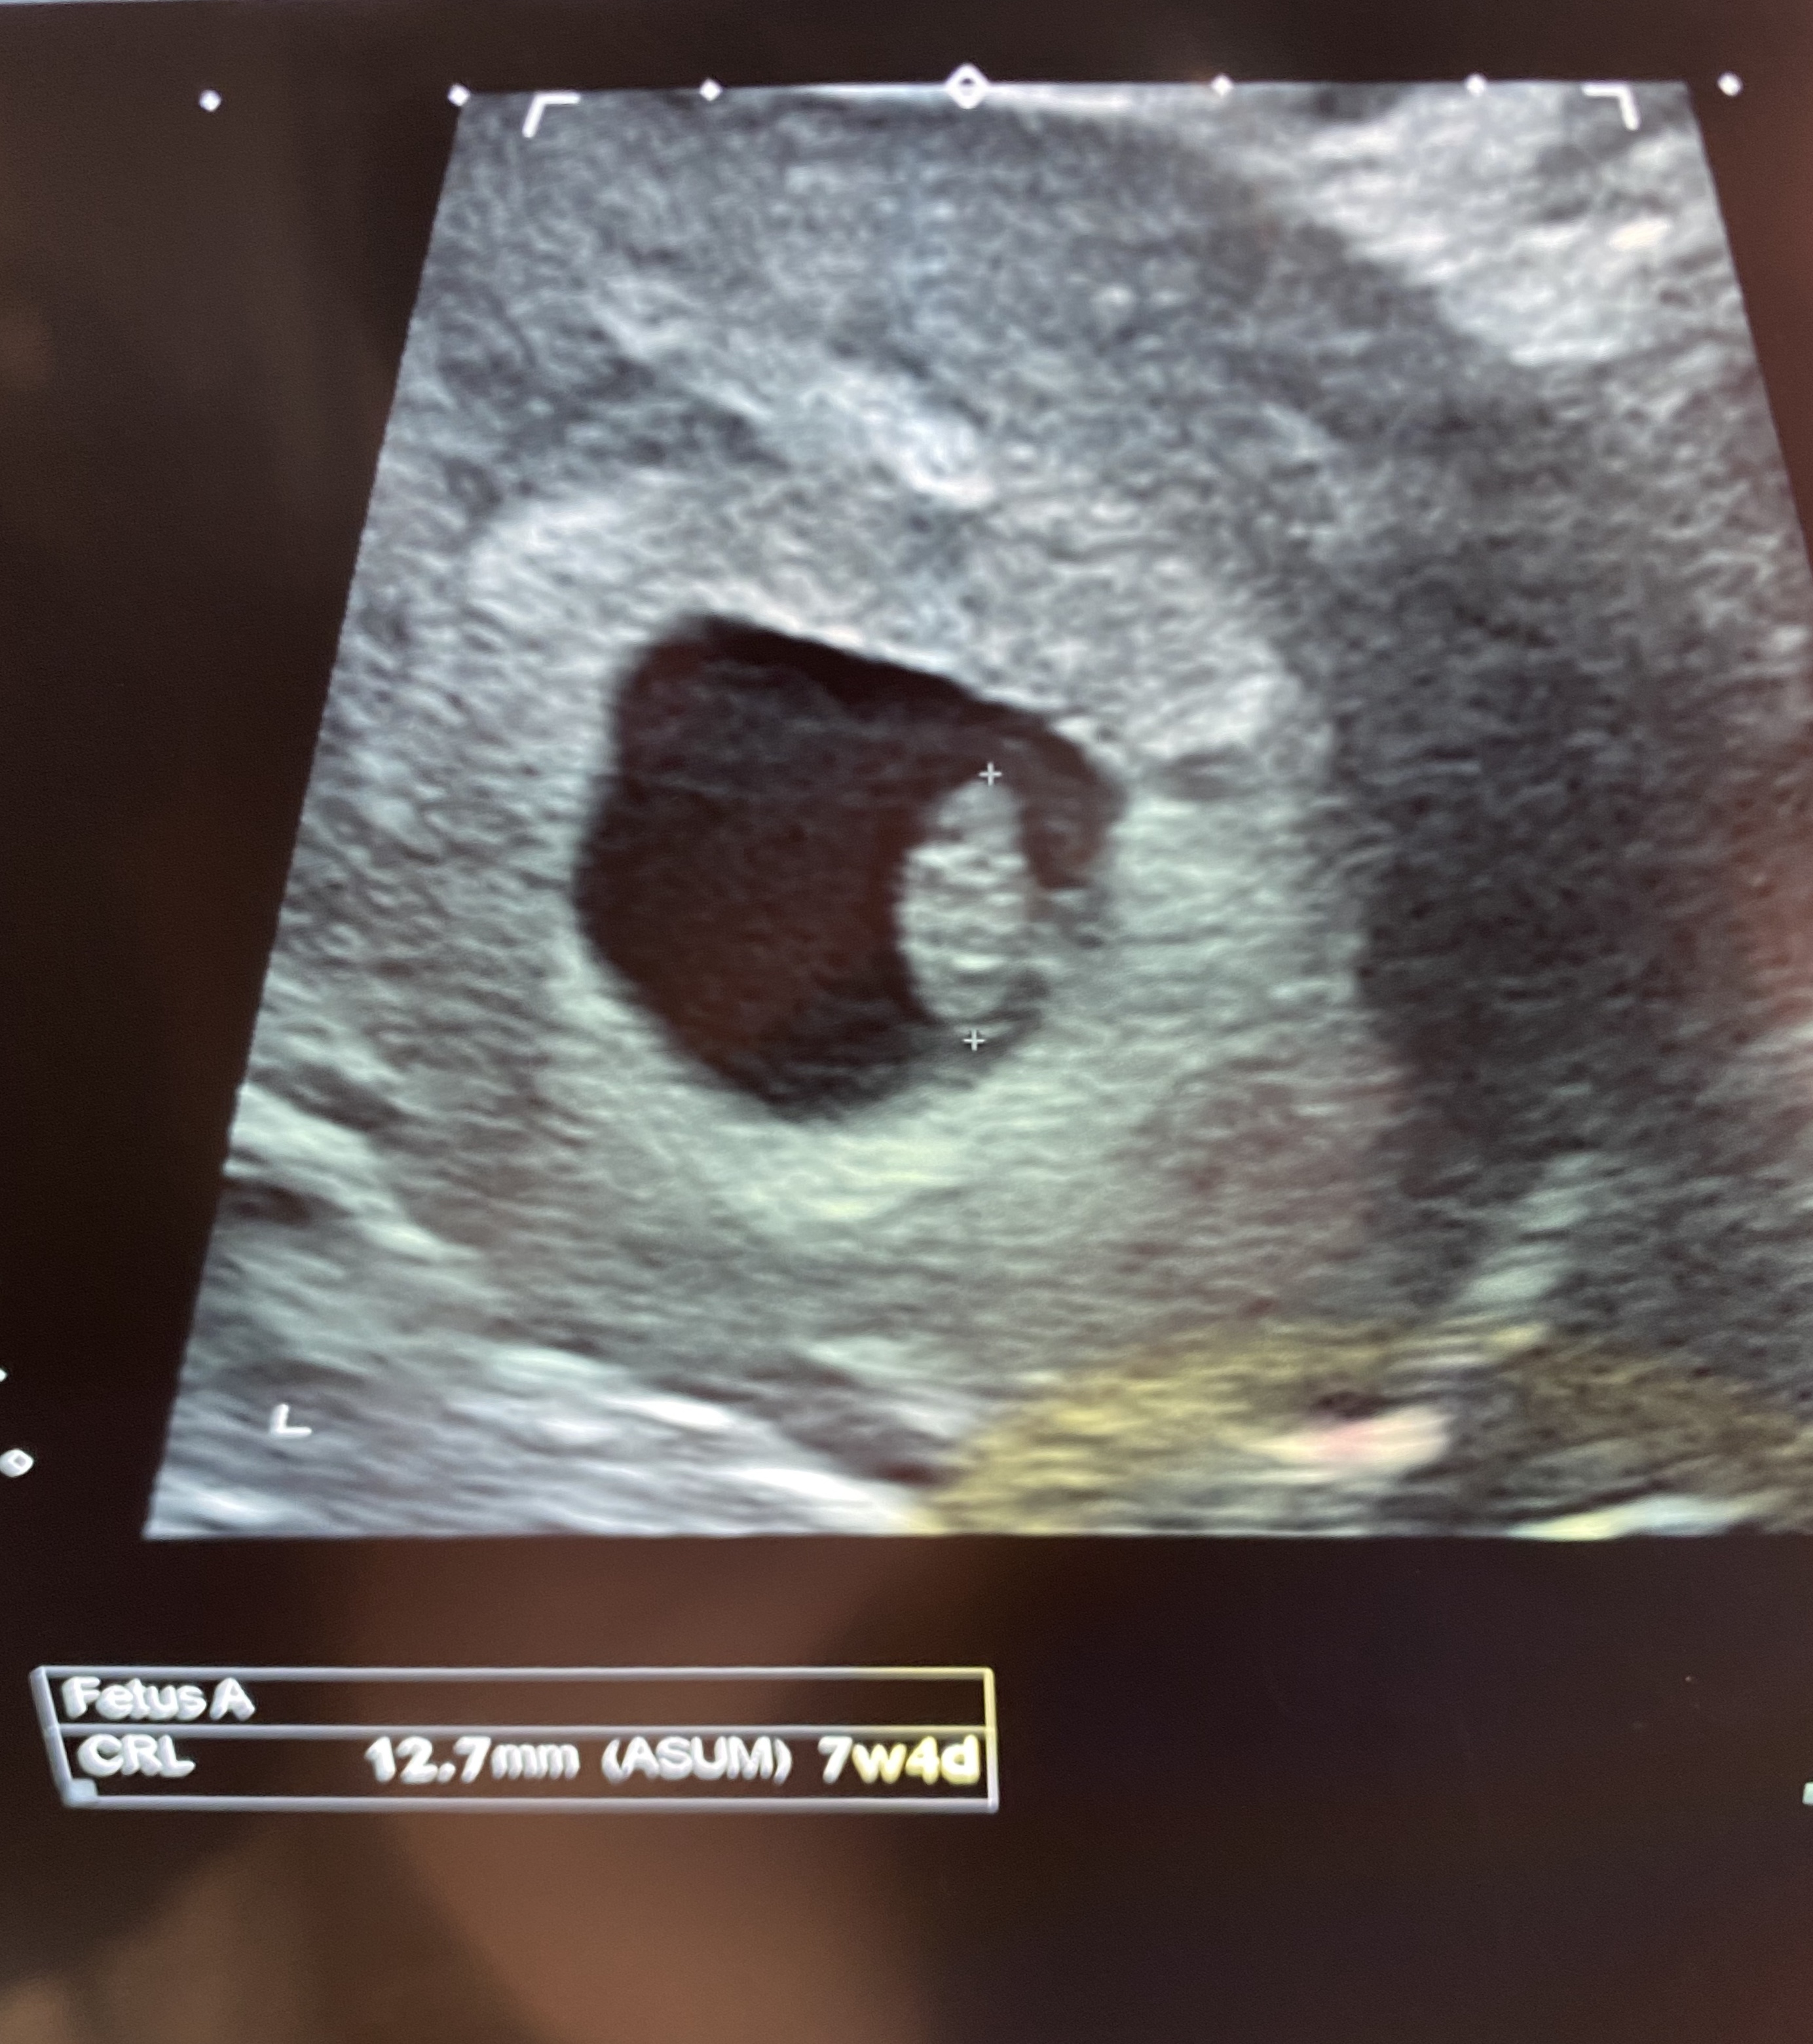

I’m currently 7w4d.

Anyway here are a couple images from the scan, it was an abdominal one. Anyone have any Ramzi guesses? We’re going to stay team green but I like to hear guesses, just for fun :)